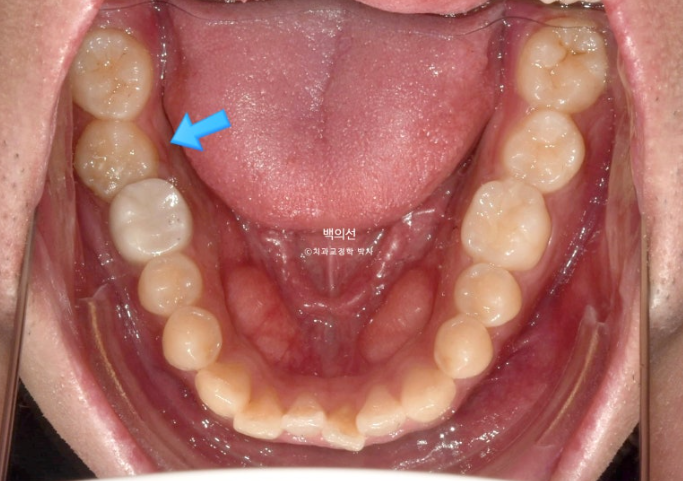

앞니가 삐뚤하고 소위 나비치아 입니다. 맨 뒤 큰어금니가 바깥으로 덧니처럼 뻗쳐있습니다.

교합면 사진에서 나비치아와 바깥으로 나가있는 두번째 큰어금니가 잘 보입니다.

파란 화살표 치아끼리 엇갈려 물리는 가위교합으로 교합이 안되는 상태입니다.